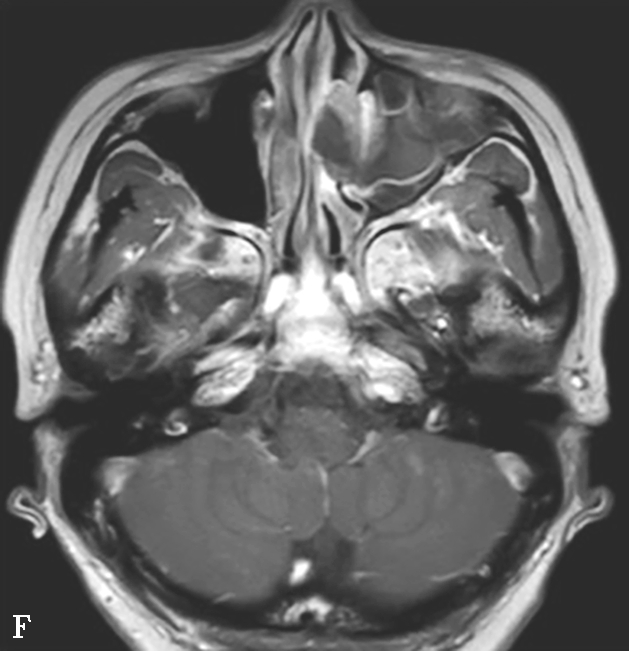

该病多发生于上颌窦和筛窦,其次为蝶窦,额窦罕见。早期表现为单侧鼻腔、鼻窦黏膜和软组织增厚,但无特异性,应密切结合临床考虑;Silverman等提出上颌窦周围脂肪间隙软组织浸润为该病较早的征象;典型表现为鼻窦内充以软组织影,窦壁及邻近颅面部骨质可出现广泛骨质破坏,但无窦腔变形,窦腔内一般无钙化;广泛侵犯眼眶、颞下窝、翼腭窝、硬腭、颅面部软组织等邻近结构,严重者可侵犯颅内,出现脑膜炎、脑炎、脑脓肿、脑梗死等(图1-3-23A、B)。

2.MRI表现

T 1 WI多为低或等信号,T 2 WI多为高信号,增强后有明显强化。MRI能更清楚显示眼眶、颅内、海绵窦等鼻外蔓延范围,为治疗方案选择提供依据,对术后随访也有很大帮助(图1-3-23C~E)。

图1-3-23 急性侵袭性真菌性鼻窦炎

A、B.横断面、冠状面CT骨窗,示双侧蝶窦、后组筛窦软组织影,密度不均,窦壁骨质硬化伴局部骨质破坏,累及双侧圆孔、翼管;C~E.MRI横断面T 1 WI、T 2 WI、T 1 WI+FS+C,示双侧蝶窦、后组筛窦内混杂长T 1 、长T 2 信号,窦腔内见斑片状短T 1 、短T 2 信号影,增强扫描边缘强化,前颅底脑膜增厚强化